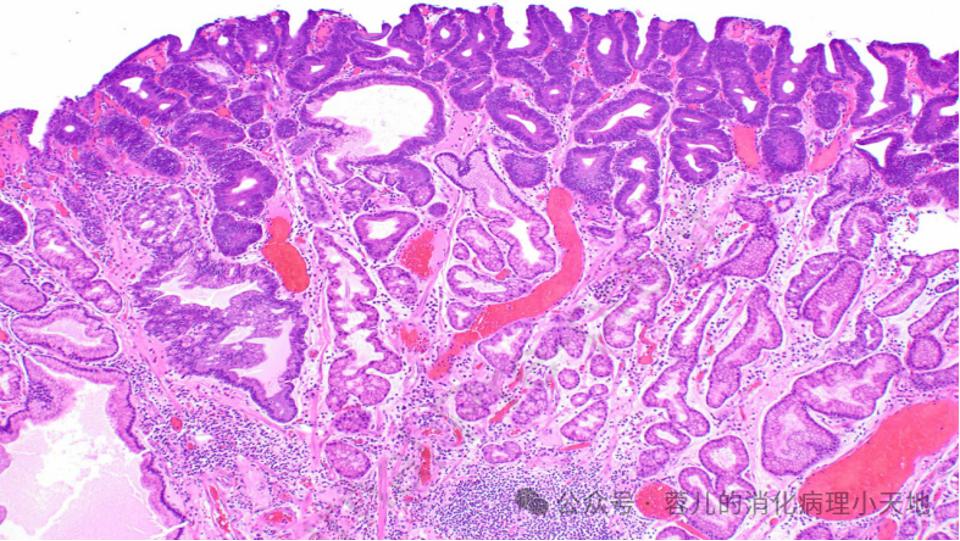

组织学+免疫表型:紧密排列的管状结构,腺管上皮细胞胞质泡沫状,核圆形均匀,表达MUC6和MUC5

幽门腺腺瘤由紧密排列的管状结构组成,管壁由立方细胞构成,细胞具有黏液性胞质和圆形、均匀的核

临床背景:散发性胃型胃泌素瘤(PGA)常伴自身免疫性胃炎相关的幽门腺化生,FAP相关PGA多发生于未发生炎症胃黏膜

分子特征:携带GNAS、KRAS、APC突变